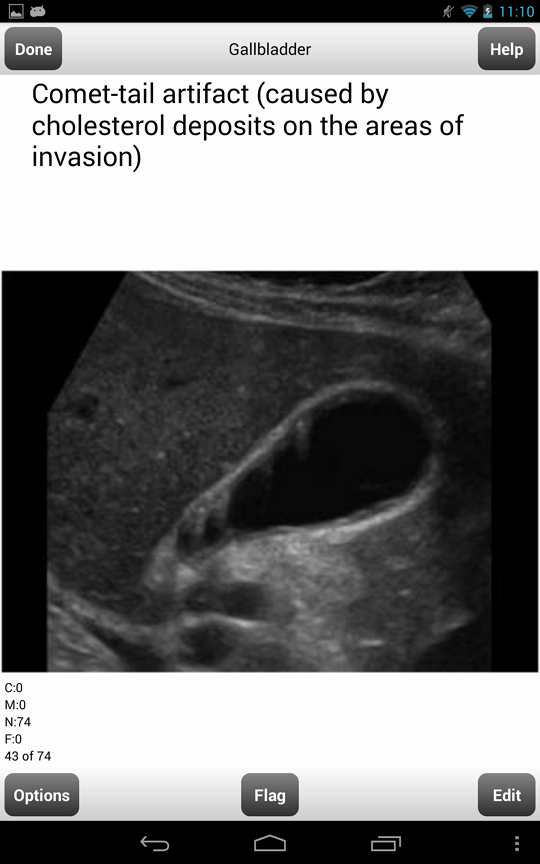

The program contains 778 flashcards that will help you study and pass the ARDMS OB/GYN boards to become a Registered Diagnostic Medical Sonographer. Here are the topics and flashcards included in this program: Fertility - 26 flashcards General GYN - 54 flashcards IUDs - 6 flashcards Ovarian Neoplasms - 63 flashcards Uterine Abnormalities - 41 flashcards 1st Trimester - 62 flashcards Abdominal Wall Defects - 18 flashcards Abortions - 6 flashcards Amniotic fluid - 11 flashcards Anomalies - 11 flashcards Chest - 30 flashcards Doppler - 7 flashcards Ectopics - 7 flashcards Embryology - 13 flashcards GI - 28 flashcards General OB - 20 flashcards Genetics - 35 flashcards Gest. Trophoblastic Disease - 5 flashcards Head - 64 flashcards Heart - 16 flashcards Hydrops - 10 flashcards IUGR - 16 flashcards Kidneys - 40 flashcards Placenta - 38 flashcards Skeletal - 29 flashcards Trisomies - 31 flashcards Twins - 29 flashcards Umbilical Cord - 19 flashcards OB/GYN Images Quiz - 43 Total of 778 high-quality flashcards to help you pass the ARDMS OB/GYN registry. The cards were created by certified RDMS sonographers who easily and successfully passed their ARDMS OB/GYN registry. The program itself offers various features and options for a great and convenient learning environment which include: - Ability to Randomize cards - Can Flag cards for later use - Grade cards by using gestures - Study only missed cards, only new cards, only correct cards, flagged cards, or study all cards - Study all categories or selected categories - Timed mode to automatically flip card and advance cards. Ability to edit and delete cards - Convenient statistics panel to see progress - Can change background color and text color - Can change text size - Can see back of card first You can try out our Lite version to see the features and how to use the program.